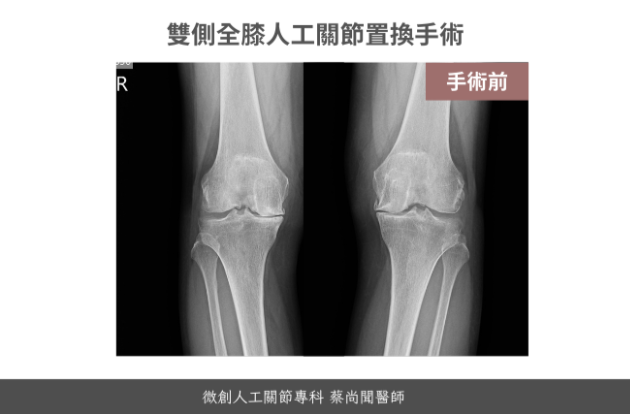

黃女士84歲

她是一位很認真的病患,事先做了很多功課,還辛苦跑了門診兩次為了當面再次會談確認手術細節,80多歲的年紀,整體身體狀況保持得很好,相當健康活

同時置換雙側人工膝關節的好處,在於不用經歷兩個恢復期的疼痛,然而在手術後的早期,也就是六周內,需要特別注意安全,小心不要跌倒扭到拐到受傷